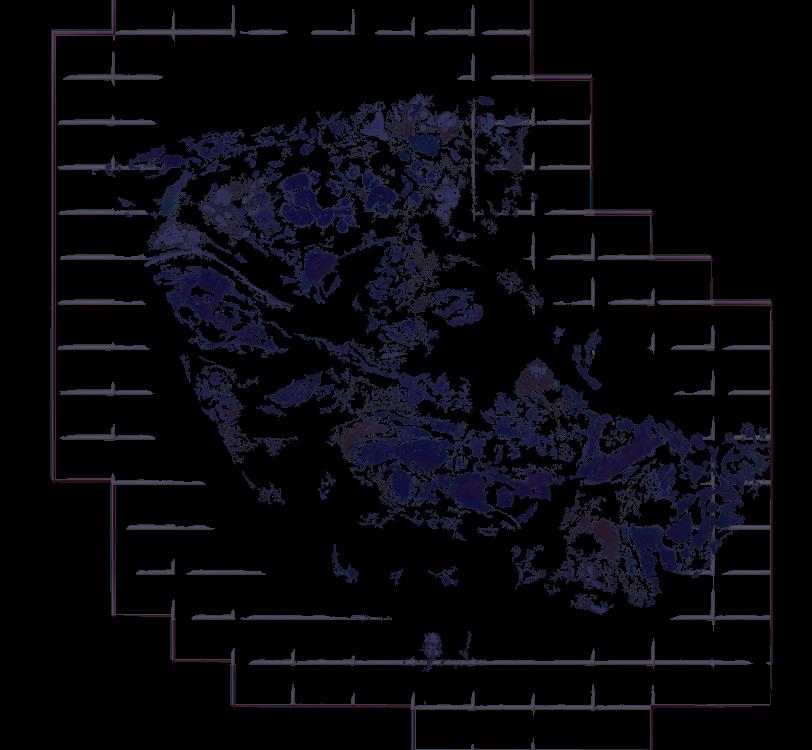

Atlas: Washington University

Breast cancer (BC) is defined by distinct molecular subtypes with different cells of origin. The transcriptional networks that characterize the subtype-specific tumor-normal lineages are not established. In this work, we applied bulk, single-cell and single-nucleus multi-omic techniques as well as spatial transcriptomics and multiplex imaging on 61 samples from 37 patients with BC to show characteristic links in gene expression and chromatin accessibility between BC subtypes and their putative cells of origin. Regulatory network analysis of transcription factors underscored the importance of BHLHE40 in luminal BC and luminal mature cells and KLF5 in basal-like tumors and luminal progenitor cells. Furthermore, we identify key genes defining the basal-like (SOX6 and KCNQ3) and luminal A/B (FAM155A and LRP1B) lineages. Exhausted CTLA4-expressing CD8+ T cells were enriched in basal-like BC, suggesting an altered means of immune dysfunction. These findings demonstrate analysis of paired transcription and chromatin accessibility at the single-cell level is a powerful tool for investigating cancer lineage and highlight transcriptional networks that define basal and luminal BC lineages.